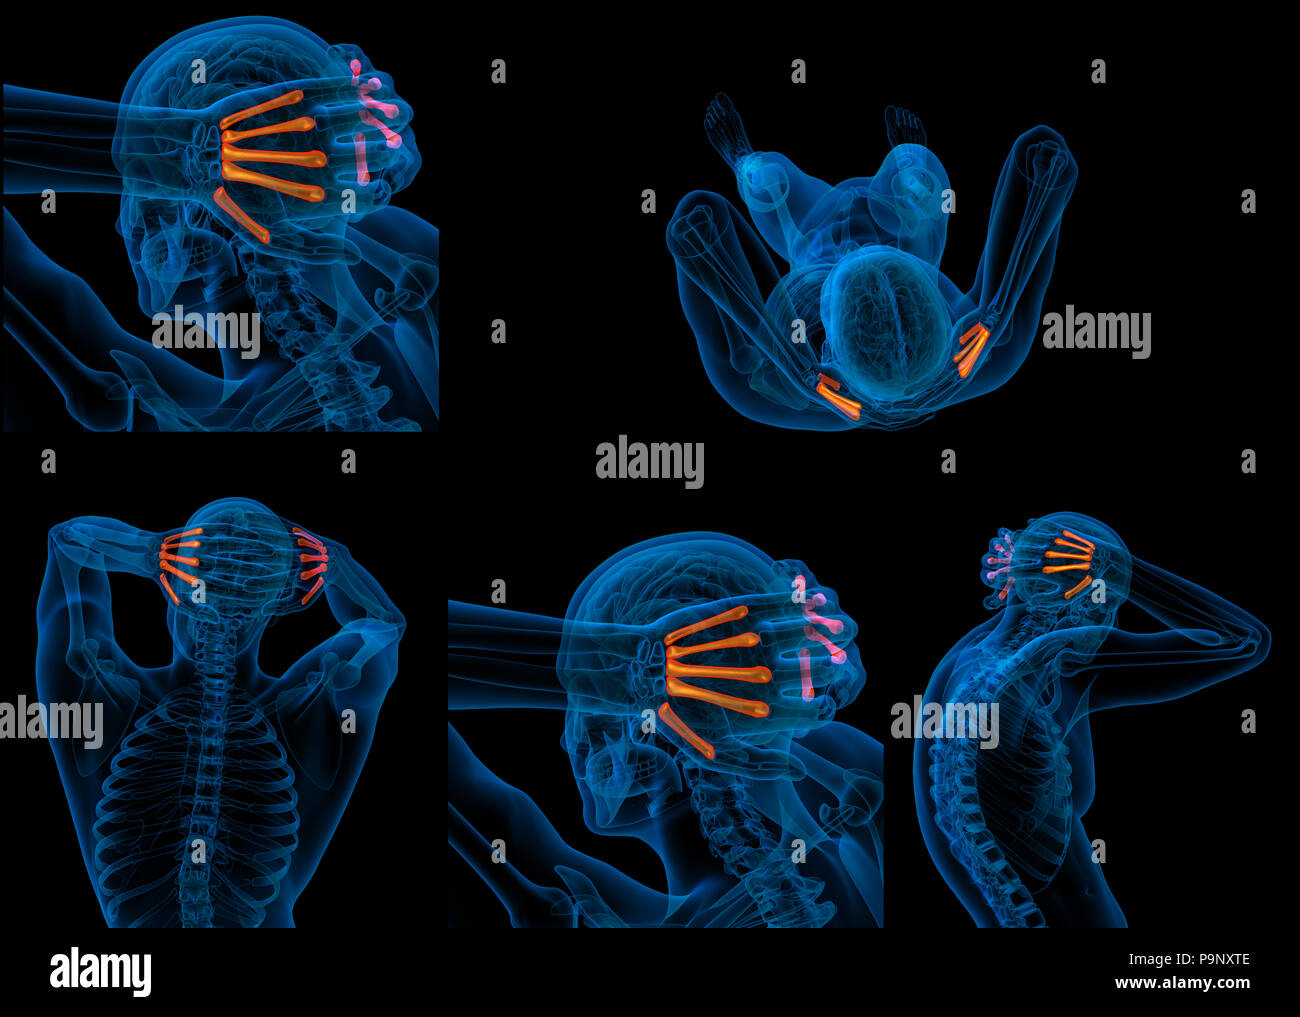

3d rendering of metacarpal Stock Photohttps://www.alamy.com/image-license-details/?v=1https://www.alamy.com/3d-rendering-of-metacarpal-image212538382.html

3d rendering of metacarpal Stock Photohttps://www.alamy.com/image-license-details/?v=1https://www.alamy.com/3d-rendering-of-metacarpal-image212538382.htmlRFP9NXTE–3d rendering of metacarpal